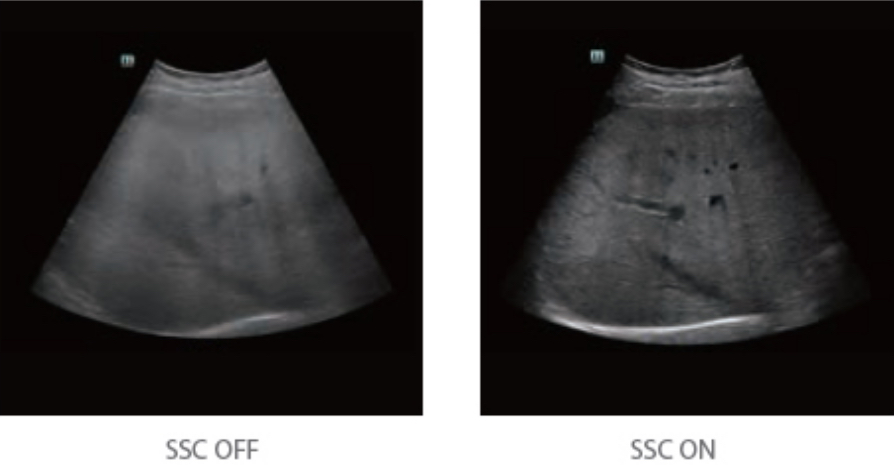

By retrospectively analyzing complete channel data stored in channel data memory, the Resona 6 is able to intelligently choose the optimal sound speed to improve image accuracy even with tissue variation, allowing for adaptive tissue-specific optimization.